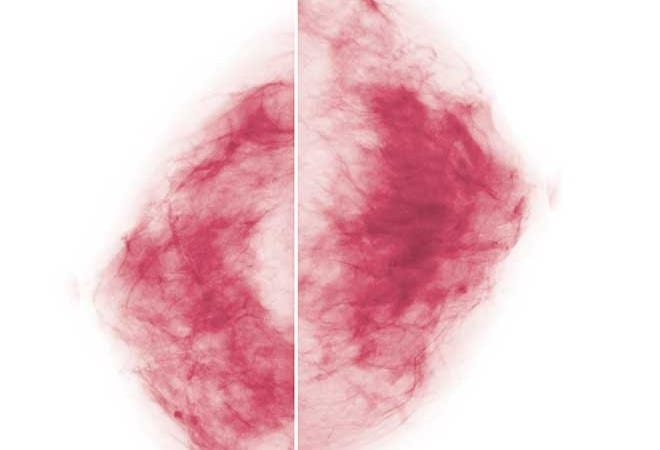

“The other hot topic is the three-dimensional mammogram, which is called tomosynthesis,” Hahs says. Both 2-D and 3-D images can find cancer when it is in the form of calcifications, which are almost like grains of sand, Appleton says. “That is a victory for mammography because those cancers are not invasive yet.”

But tomosynthesis, 3-D imaging, magnifies the clarity of the examination, creating images of all breast tissues as seen from one view—somewhat like peering through all the pages of a closed book at one time, Appleton explains. “With tomosynthesis, we create a volume of data. We literally can page through the breast in 1-millimeter slices (a millimeter is thinner than a dime).”

There’s no question that 3-D imaging exposes abnormalities that couldn’t be seen before, Appleton says. And it minimizes the need for call-back exams. “Women with dense breasts are good candidates for tomosynthesis mammograms,” Hahs adds. “Insurance companies vary on what they will pay for. Some are completely on board and some are not.”

The most comprehensive form of breast imagery is the 3-D variety, which uses ultrasound to detect abnormalities that are still tiny specks or hidden in dense tissue. “Tomosynthesis allows us to see multiple slices through the tissue,” says Dr. Deborah Wadsworth, a radiologist at The Breast Center at Mercy Hospital. “A 2-D image (the typical 2-D mammogram) can miss a lot of details. Three-dimensional imaging is like flying through this very dense forest and seeing every tree. We can take the computer mouse and scroll back and forth and around the image.”

Ultrasound is the mode of choice for women with dense breasts, she says. “They have glandular tissue that obscures smaller tumors on the (X-ray) mammogram. We are better able to see some tumors on ultrasound and other tumors with mammography.”